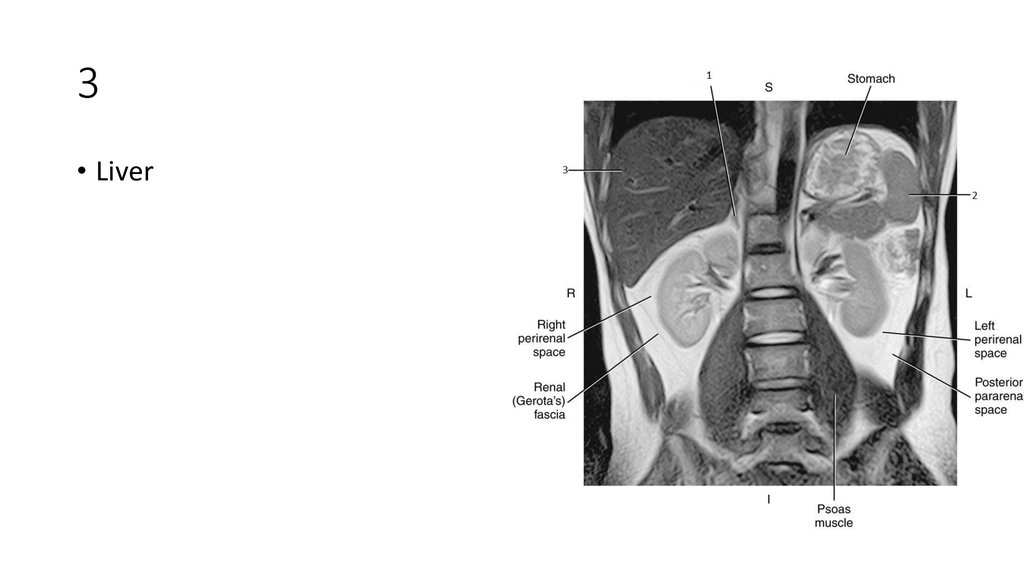

2. 1

3. 1

• Liver

4. 2

5. 2

• Spleen

6. 3

7. 3

• Aorta

8. 4

9. 4

• Inferior Vena Cava (IVC)

10. 1

11. 1

• Right Adrenal Gland

12. 2

13. 2

14. 3

15. 3